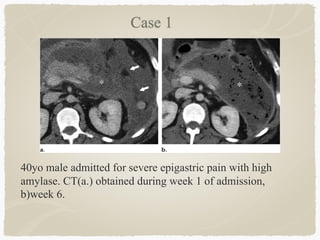

40yo male admitted for severe epigastric pain with high

amylase. CT(a.) obtained during week 1 of admission,

b)week 6.